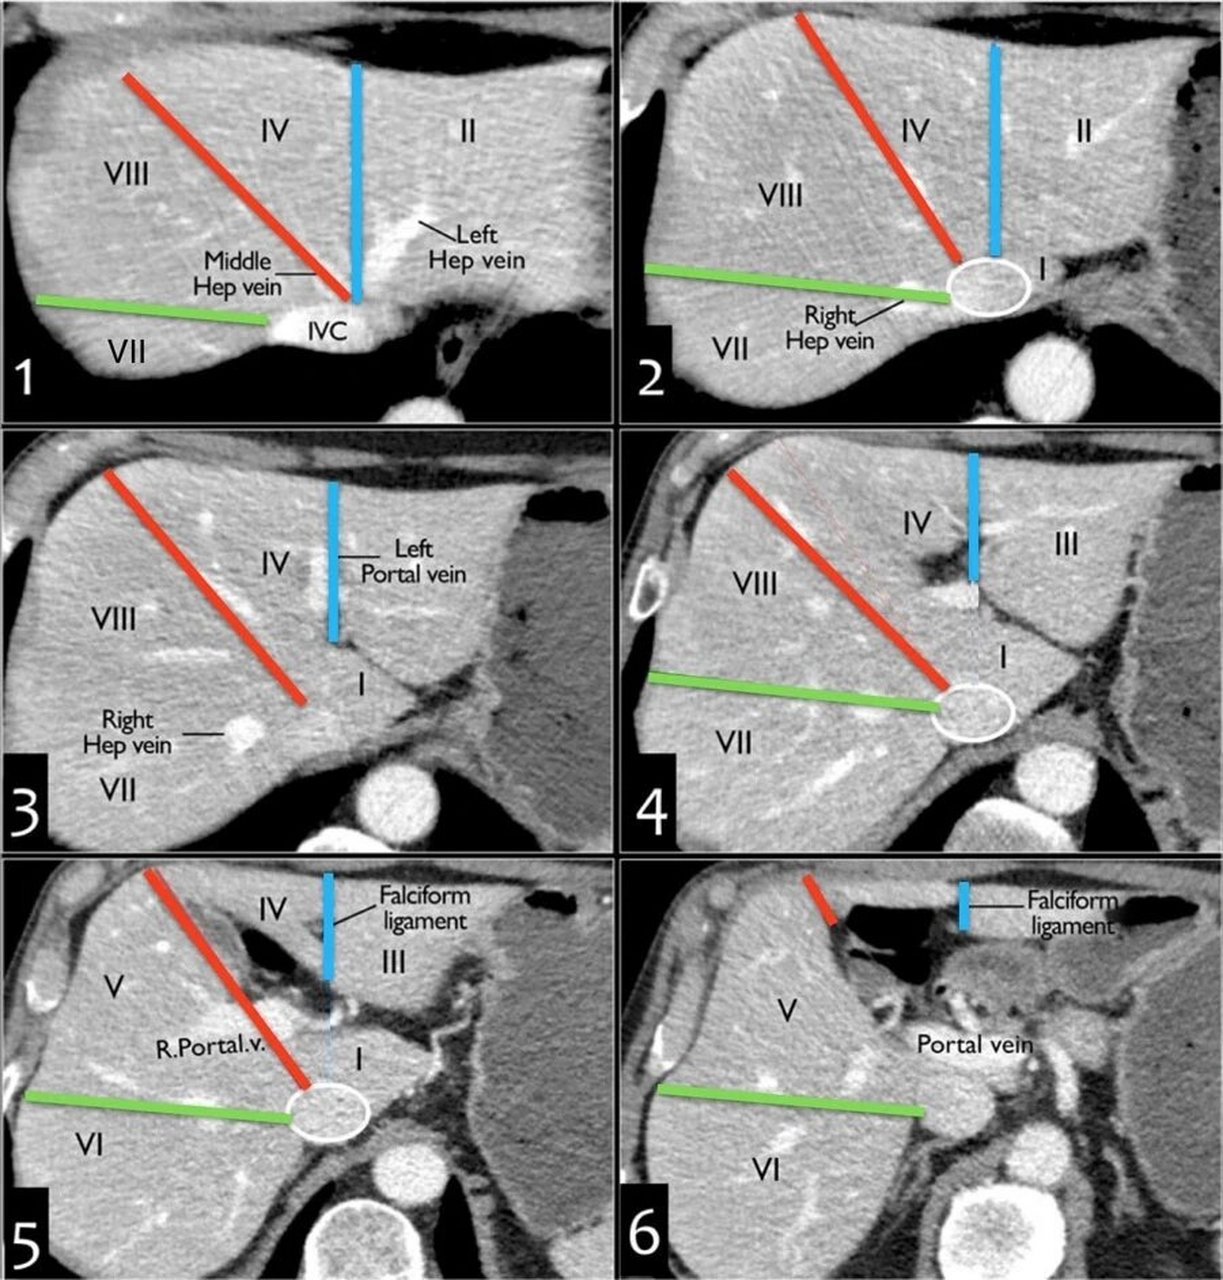

肝脏分段ct解剖 左肝:外侧段(s2/s3)与内侧段(s4a/s4b)沿镰状韧带

肝脏分段口诀与ct 追踪肝静脉,尾叶单独记 肝中静脉分左右 肝右静脉分

必须收藏!最详细的肝脏ct分段解剖逐帧播放!